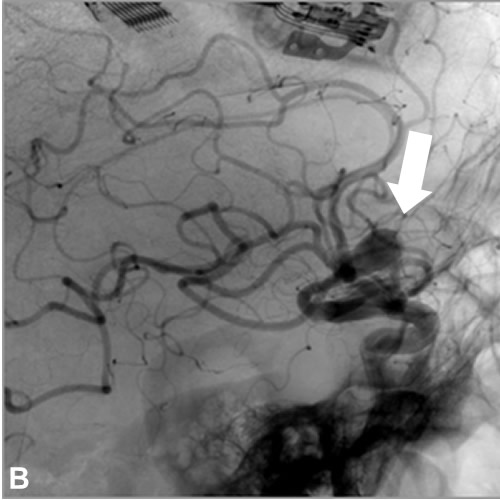

A, B: Series angiográficas en proyecciones AP y L de arteria carótida interna izquierda, observándose aneurisma de arteria comunicante anterior (flechas negras). C: Reconstrucción 3D. Nótese origen adyacente al cuello aneurismático y trayecto de arteria cerebral anterior accesoria (flechas blancas).

En 2017 sufrió traumatismo craneal leve en accidente de tráfico, motivando la realización de neuroimagen en la que se identificó un aneurisma de arteria comunicante anterior. Posteriormente se realizó arteriografía diagnóstica, confirmando la presencia de un aneurisma sacular polilobulado de arteria comunicante anterior, con diámetros aproximados de 13mm x 9 mm y cuello de 4 mm. Como variante de la normalidad, el paciente presenta además una duplicación del segmento A2 abarcando el trayecto pericalloso, evidente en las series angiográficas de arteria carótida interna izquierda, cuyo origen se encuentra en íntima relación con el cuello aneurismático, y que podría corresponder a una persistencia de la arteria mediana del cuerpo calloso (variante con una prevalencia de entre 3 y 6%1,2).